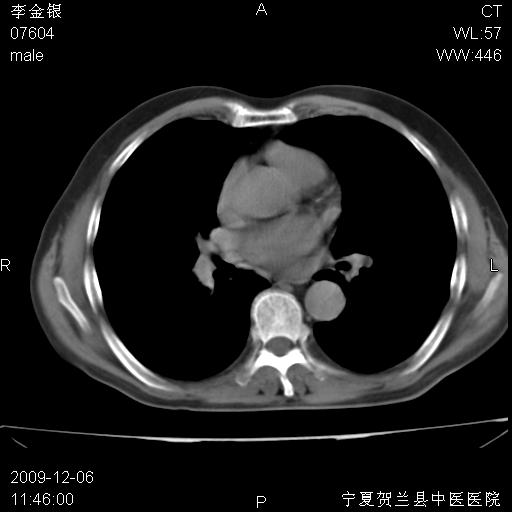

该病人 ,男,62岁,主因咳痰带血两天

考虑右肺中心型肺癌伴阻塞性肺炎及右肺门淋巴结转移,建议纤维支气管镜进一步检查。

支气管壁明显增厚 管腔狭窄,腔静脉后多个淋巴肿大,结合年龄病史考虑右肺上叶中央型肺癌并阻塞性肺炎

右肺上叶后段支气管阻塞,右上肺门占位,相应肺段阻塞性肺炎,右肺门有淋巴结肿大。诊断右肺上叶中心型肺癌,阻塞性肺肺炎、右肺门淋巴结转移。

符合中央型肺癌的ct表现并肺出血。但有一点腔静脉后有一钙化的淋巴结啊

右肺中心型肺癌伴阻塞性肺炎及右肺门与纵膈淋巴结转移很典型,可纤维支气管镜进一步检查

右侧中央型肺癌伴纵隔内淋巴结转移考虑。

考虑右侧中央型肺癌伴右肺上叶后段阻塞性炎症、肺不张、右肺门和纵隔淋巴结肿大。

右肺上叶中心型肺癌,阻塞性肺炎、右肺门和纵隔淋巴结转移。